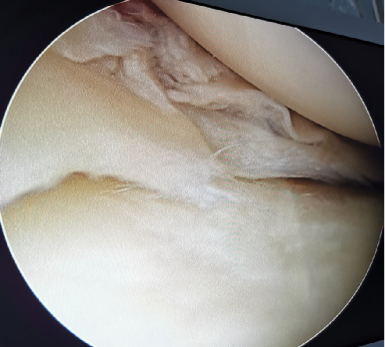

前交叉韧带断裂